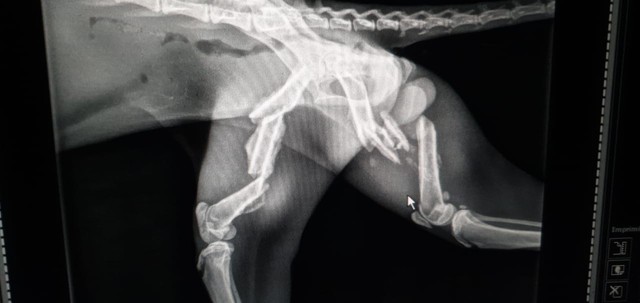

A jaguatirica aparentava estar muito cansada e não ofereceu muita resistência. Ela foi encontrada acuada em meio às plantas da casa. O animal foi levado para uma clínica veterinária de Marília, para passar por avaliação e tratamento. Exames constataram que ela sofreu fraturas nas duas patas traseiras.

No atendimento, também foi constatado que estava a jaguatirica estava magra e debilitada. Ela permanecerá internada e quando tiver condições clínicas, após sua recuperação, poderá ser devolvida à natureza.